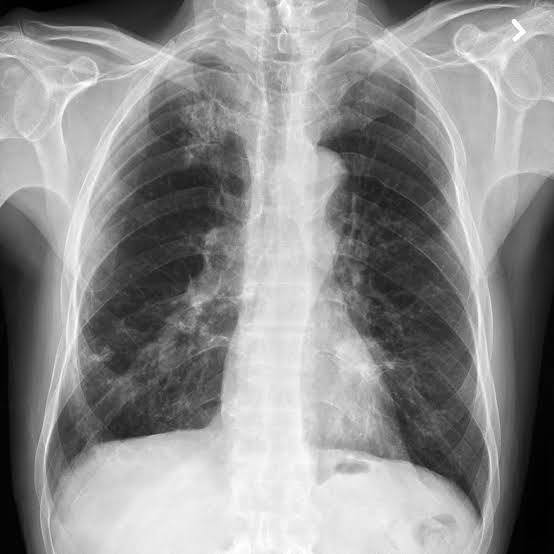

Bronchogenic carcinoma is a malignant neoplasm of the lung arising from the epithelium of the bronchus or bronchiole. Pathology. Bronchogenic carcinomas begin as a small focus of atypical epithelial cells within the bronchial mucosa.